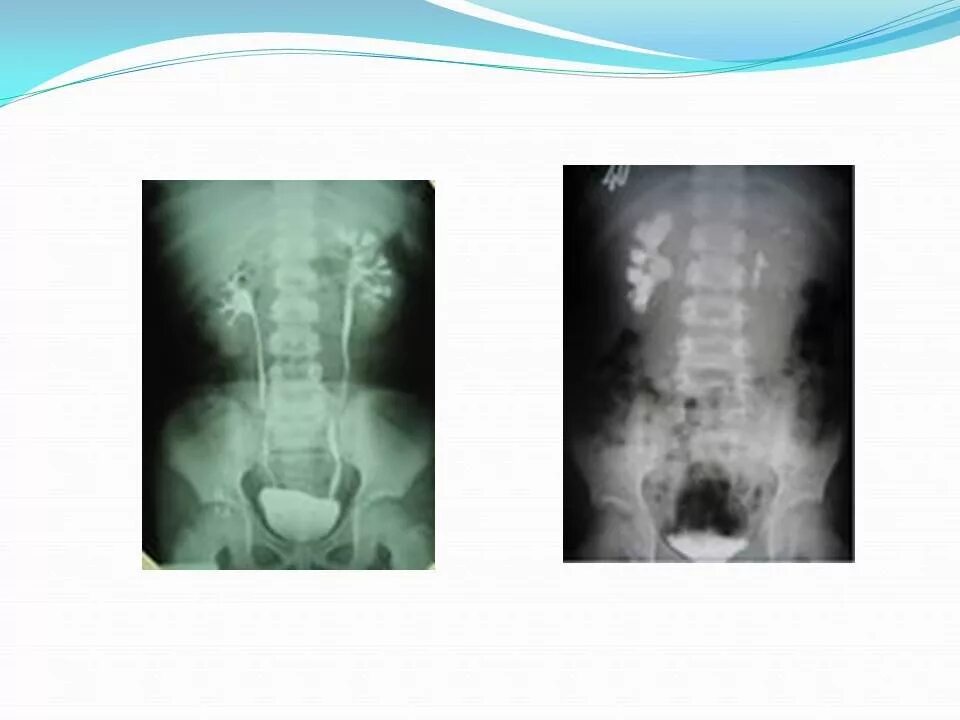

После урографии